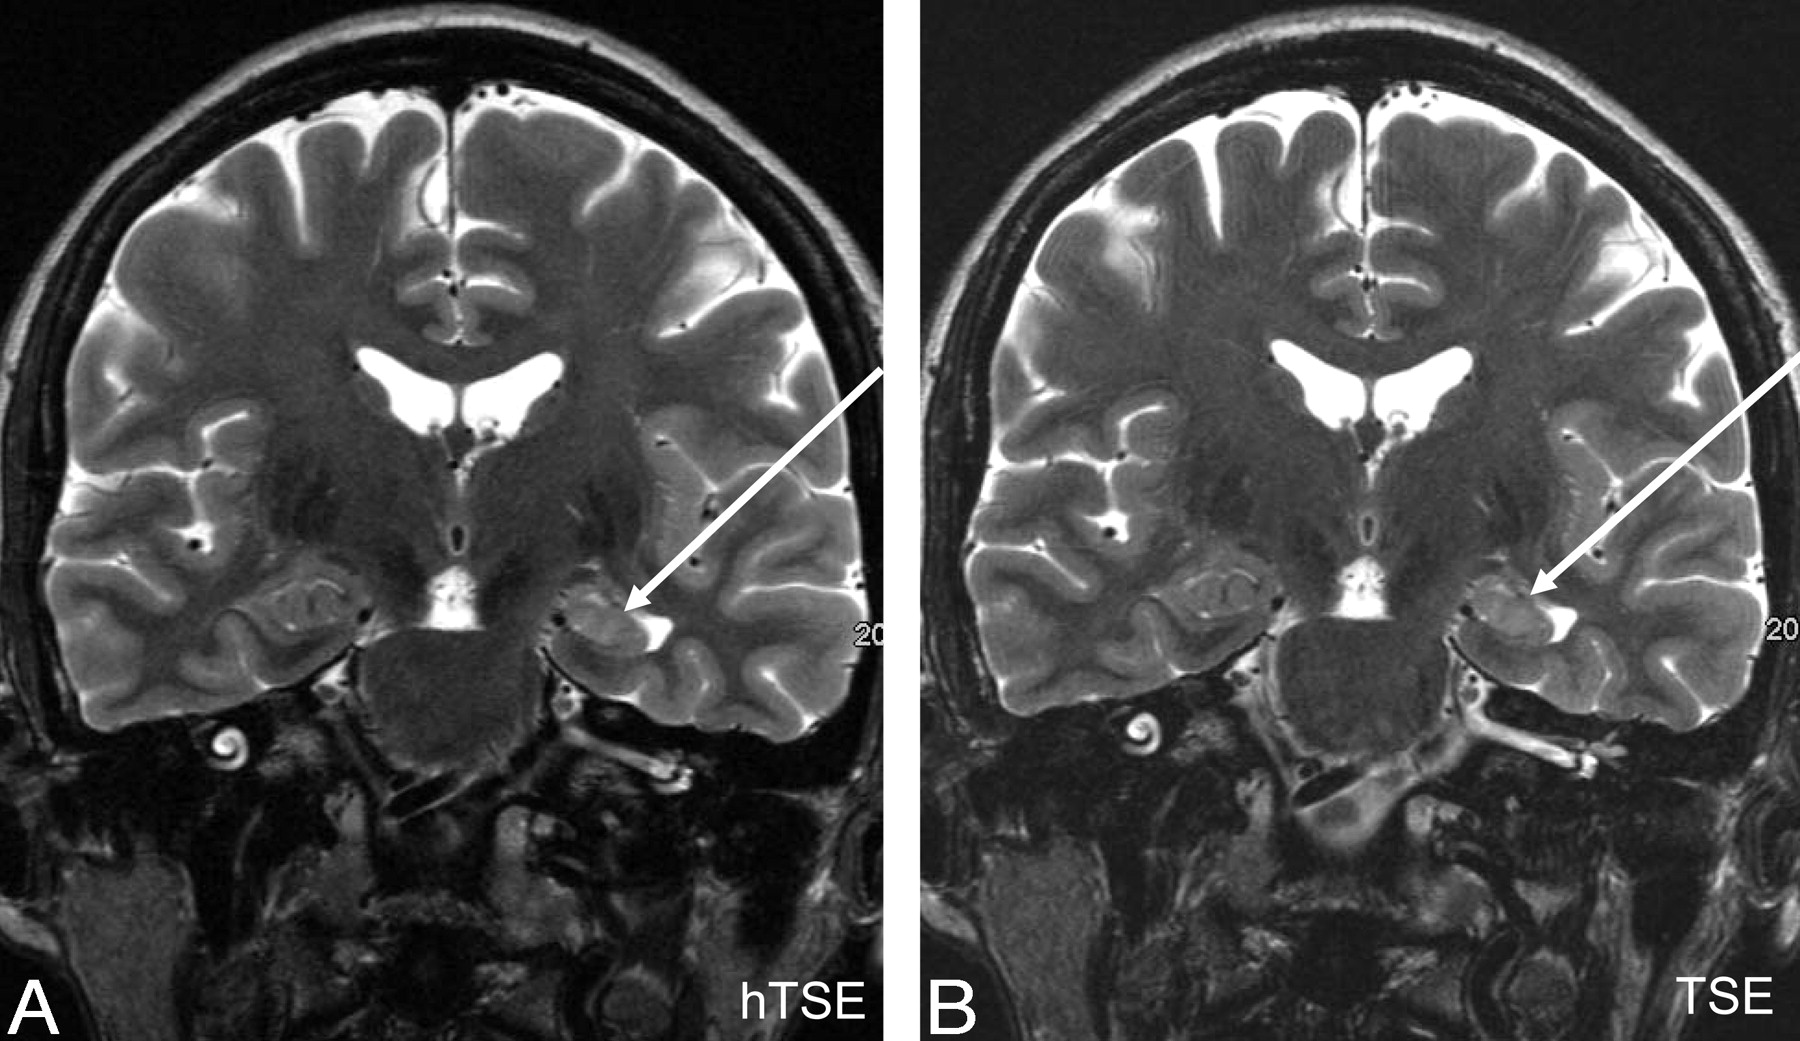

Representative cases, including 2 hyperintense lesions (a posttraumatic contusional state and a hippocampal sclerosis) and 1 hypointense lesion (cavernoma), are shown in Figs 4–⇓6, respectively.

A, hyperTSE (hTSE). B, TSE180°. The left hippocampus is atrophic and has increased signal intensity attributed to hippocampal sclerosis (arrows). This finding was confirmed by surgery. The right hippocampus shows the typical dentation, and the particular layers are visible on both sequences.